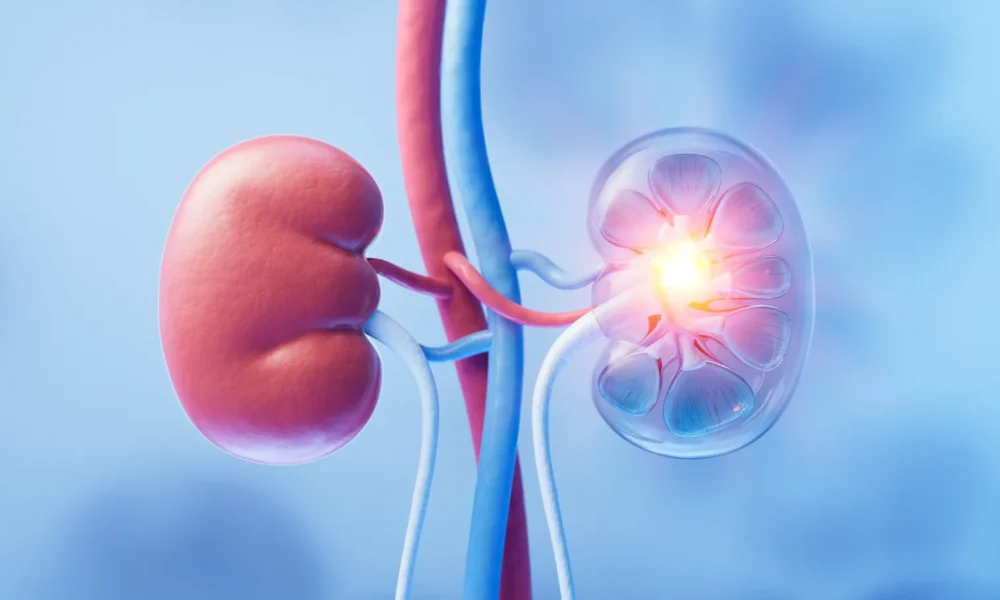

BioPharma Dive – AI / Data3 months agoMaze tumbles despite positive data for kidney disease drug

Investors had reservations about data for a drug that could compete with a candidate from Vertex in APOL1-mediated kidney disease.